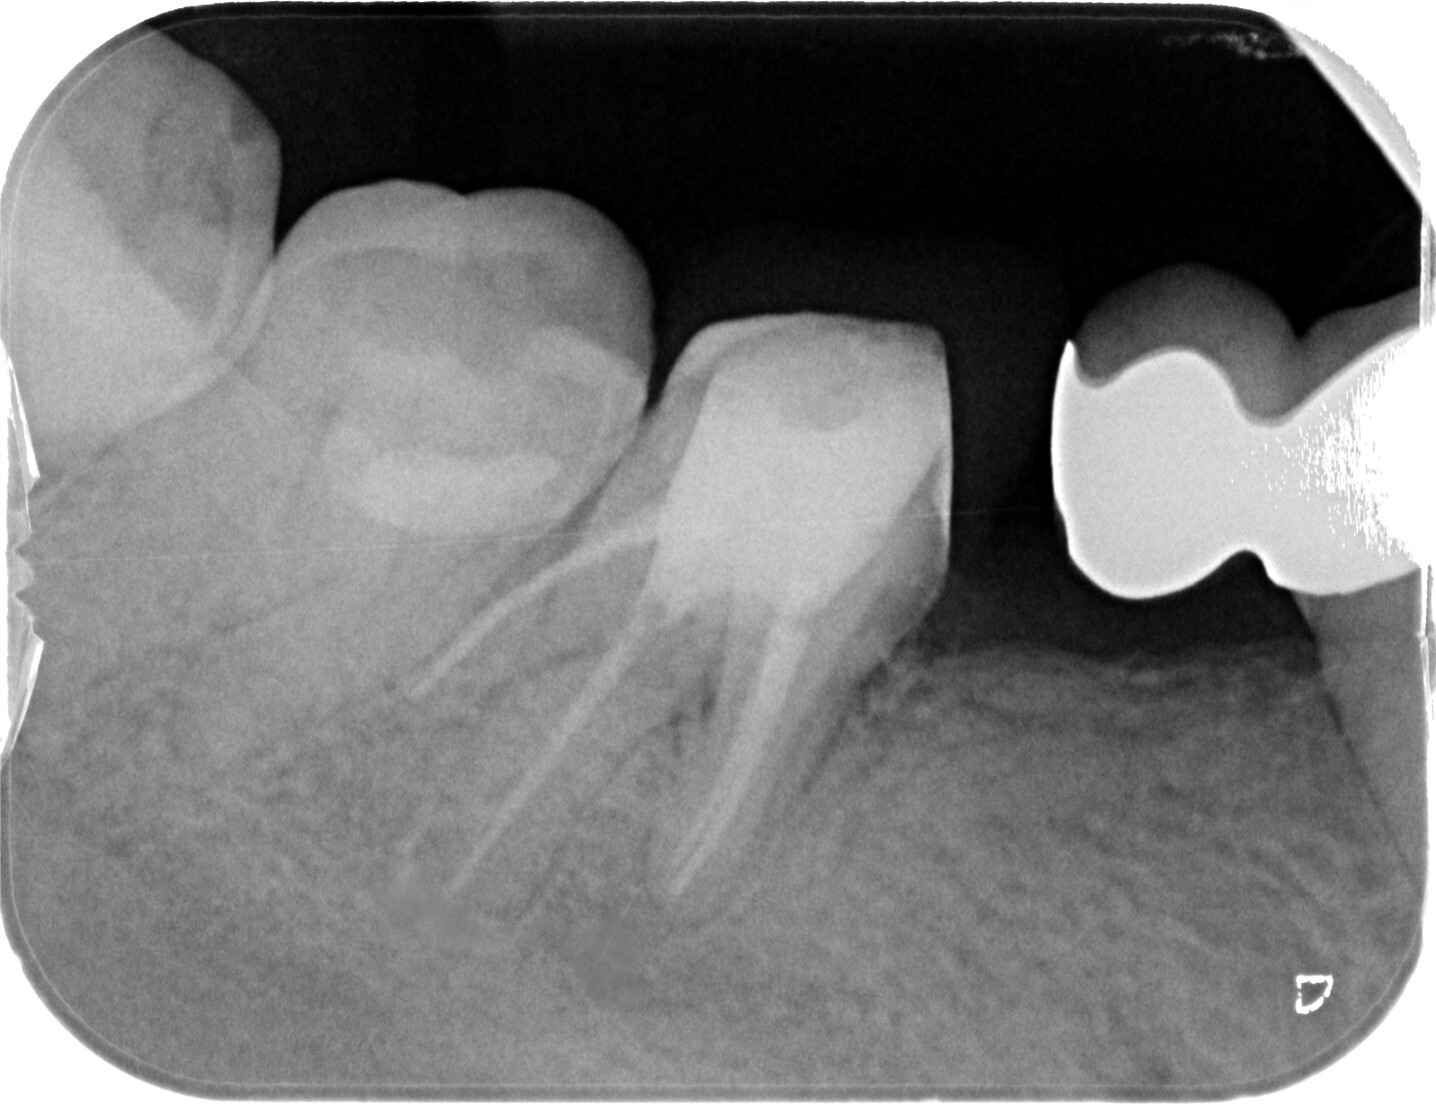

| 主訴 | 歯が折れたため来院。 |

| 治療内容 | 抜歯とともにソケットプリザベーション(歯槽骨再生療法)を行い、歯槽骨の再生を行う。その後にインプラントの埋入処置を行いました。 |

| 想定されたリスク | 再生療法を行っても、骨に置換されない場合もあり、その場合は追加的な処置もしくはインプラント埋入自体を断念しなければならない可能性もありました。 |